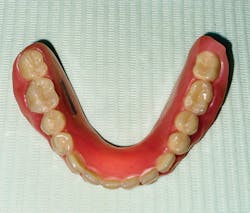

- A complete denture, which is essentially a piece of plastic that, unfortunately, most patients expect to function like real teeth due to misplaced high expectations and misunderstandings brought about by various media forums (figure 2).